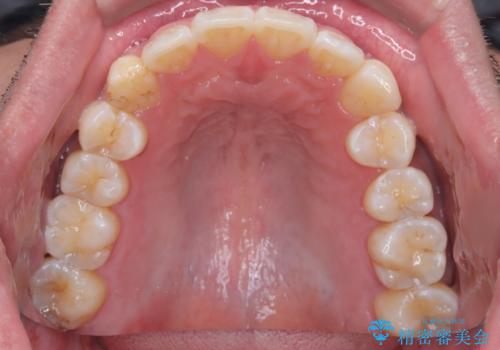

【インビザライン】前歯の凸凹を解消。

- 前歯の凸凹を主訴に来院されました。

もともと、顎が左にシフトしていたので正中が合わないことを説明した後、矯正を開始しています。

短期間で前歯のがたがたがきれいになり、満足していただけました。